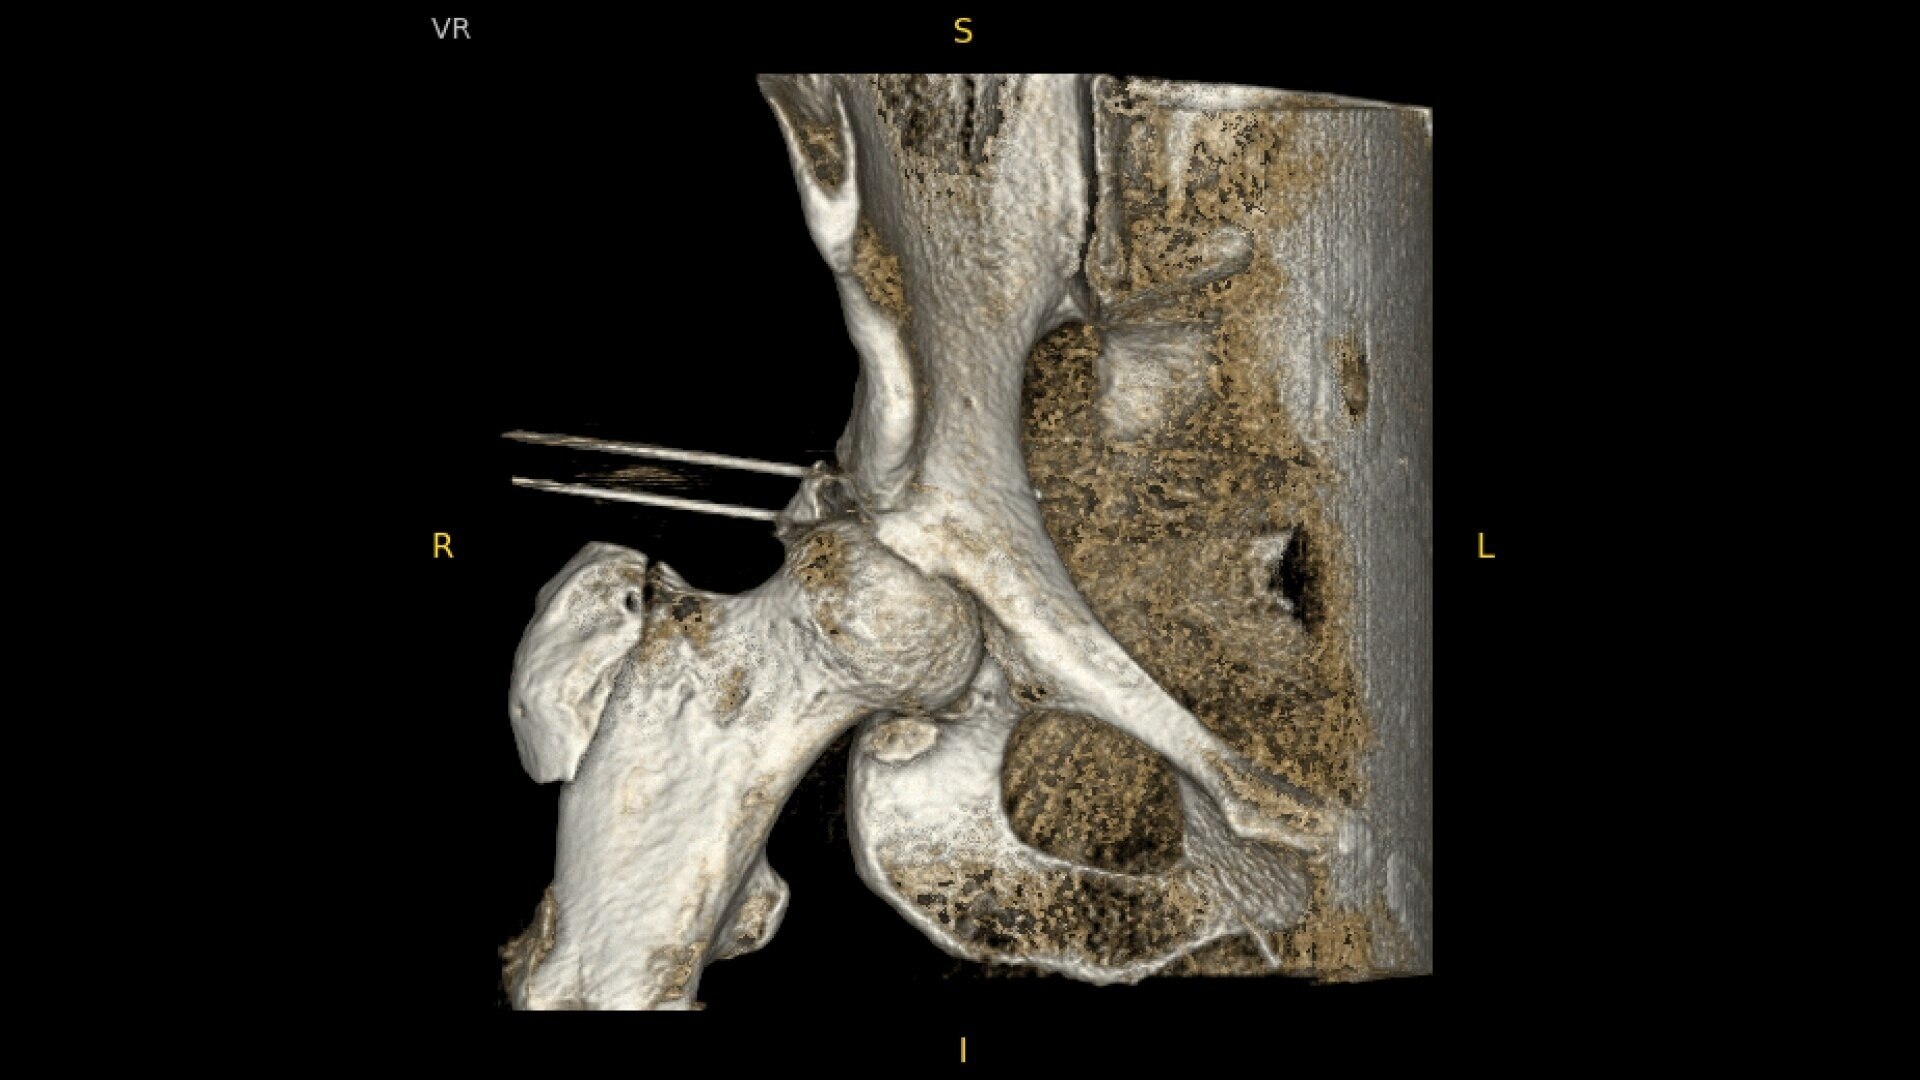

Complex orthopedic procedures require powerful imaging systems. OEC premium C-arms perform in a variety of procedures such as:

• Hip fracture fixation

• Hip replacement

Designed to bring high-definition 3D and 2D images to surgical suites and integrating into existing surgical workflows.